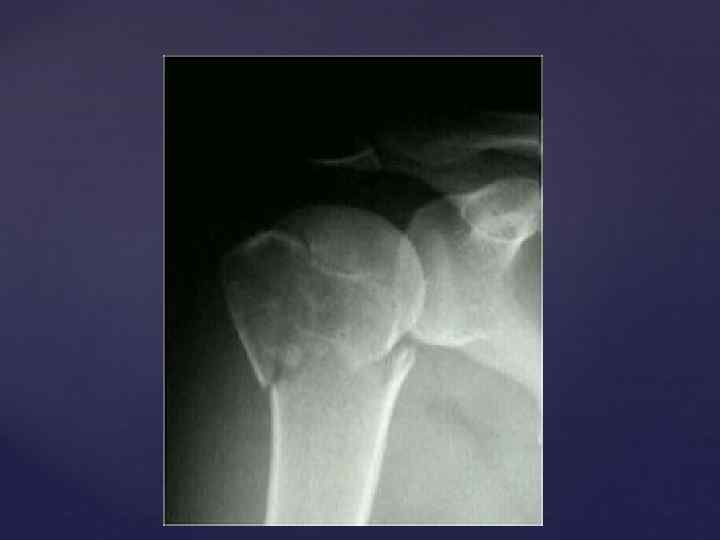

Головка плечевой кости в задней проэкции с вытянутой вдоль туловища конечностью, своей нижнемедиальной частью наслаивается на суставную впадину лопатки и проэцируется всегда выше нижней границы ее. Знание этой ретнгенологической нормы помогает распознать вывихи.

Головка плечевой кости в задней проэкции с вытянутой вдоль туловища конечностью, своей нижнемедиальной частью наслаивается на суставную впадину лопатки и проэцируется всегда выше нижней границы ее. Знание этой ретнгенологической нормы помогает распознать вывихи.

ПЛЕЧЕВОЙ СУСТАВ - появление двух т. о. в головке плечевой кости - 9 -12 мес - син-ие всех т. о в единую головку – 5 -8 лет - син-ие эпифиза и диафиза - 20 -23 года - появление множественных т. о. по краю суставной впадины лопатки – 4, 5 -5 лет - син-ие т. о. края суставной впадины – 67 лет

ПЛЕЧЕВОЙ СУСТАВ - появление двух т. о. в головке плечевой кости - 9 -12 мес - син-ие всех т. о в единую головку – 5 -8 лет - син-ие эпифиза и диафиза - 20 -23 года - появление множественных т. о. по краю суставной впадины лопатки – 4, 5 -5 лет - син-ие т. о. края суставной впадины – 67 лет